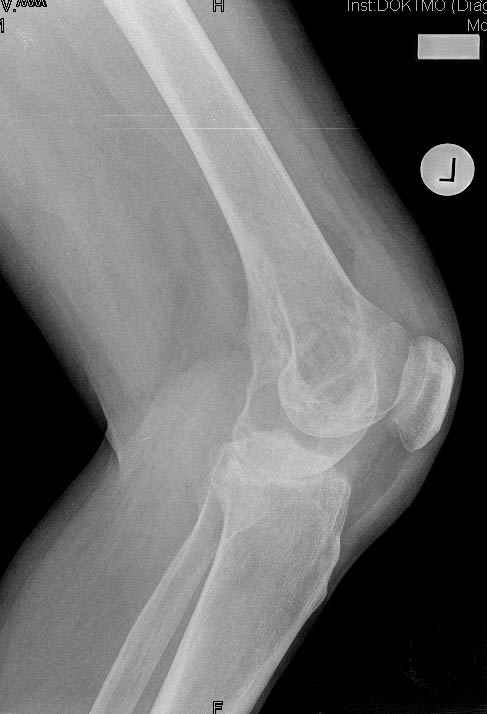

Коллеги!Окажите, пожалуйста, консультативную помощь.Мужчина, 41 год, 15 лет состоит на учете по поводу ревматоидного полиартрита, гормонзависимый (преднизолон получает нерегулярно). В процесс вовлечены крупные и мелкие суставы. 01.01.06 - без травмы наступил патологический перелом на границе н/3-с/3 бедра (перелом на фоне кистозных изменений?)

На рентгенограммах, помимо перелома, кистозные изменения на мыщелках б/берцовой кости и мыщелке бедра с другой стороны.